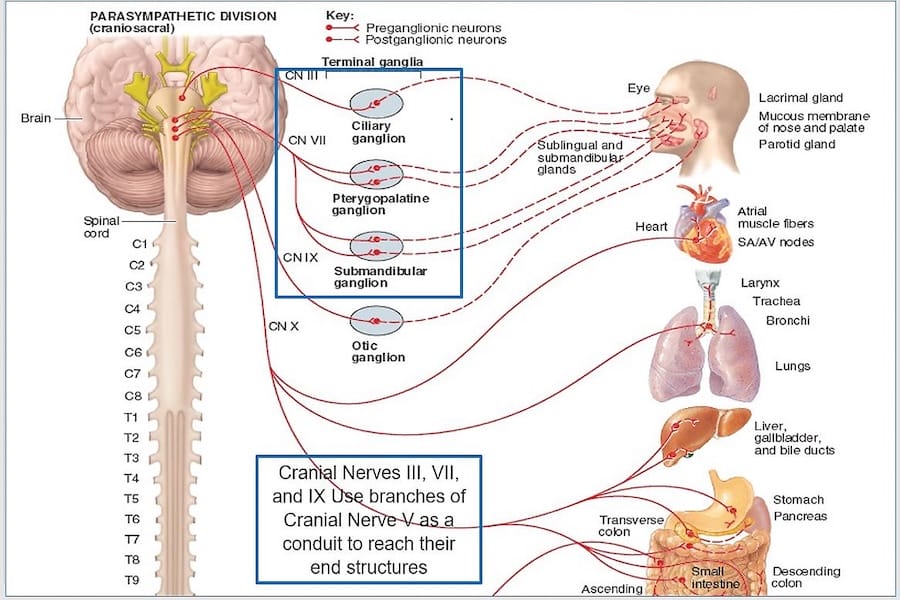

Figure 4 illustrates the extensive neural control the Trigeminal Nerve (CN V) has over chewing, swallowing, and breathing simultaneously, as CN V is used by 3 other cranial nerves (CN III, VII, IX) to reach their end structures. The posterior teeth (part of CNV, Div III) directly communicate with the center of the brain (RetF), and 4 cranial nerves to ensure food does not enter the lungs.

Figure 4 – The Trigeminal nerve aids the OculomotorTrochlear, Facial, and Glossopharyngeal nerves in reaching their end structures. Posterior tooth pulp and PDL motor fibers influence many structures that 4 cranial nerves and the RetF control. Adapted from https://quizlet.com/132746657/chapter-15-the-autonomic-nervous-system-ganglia-flash-cards/.